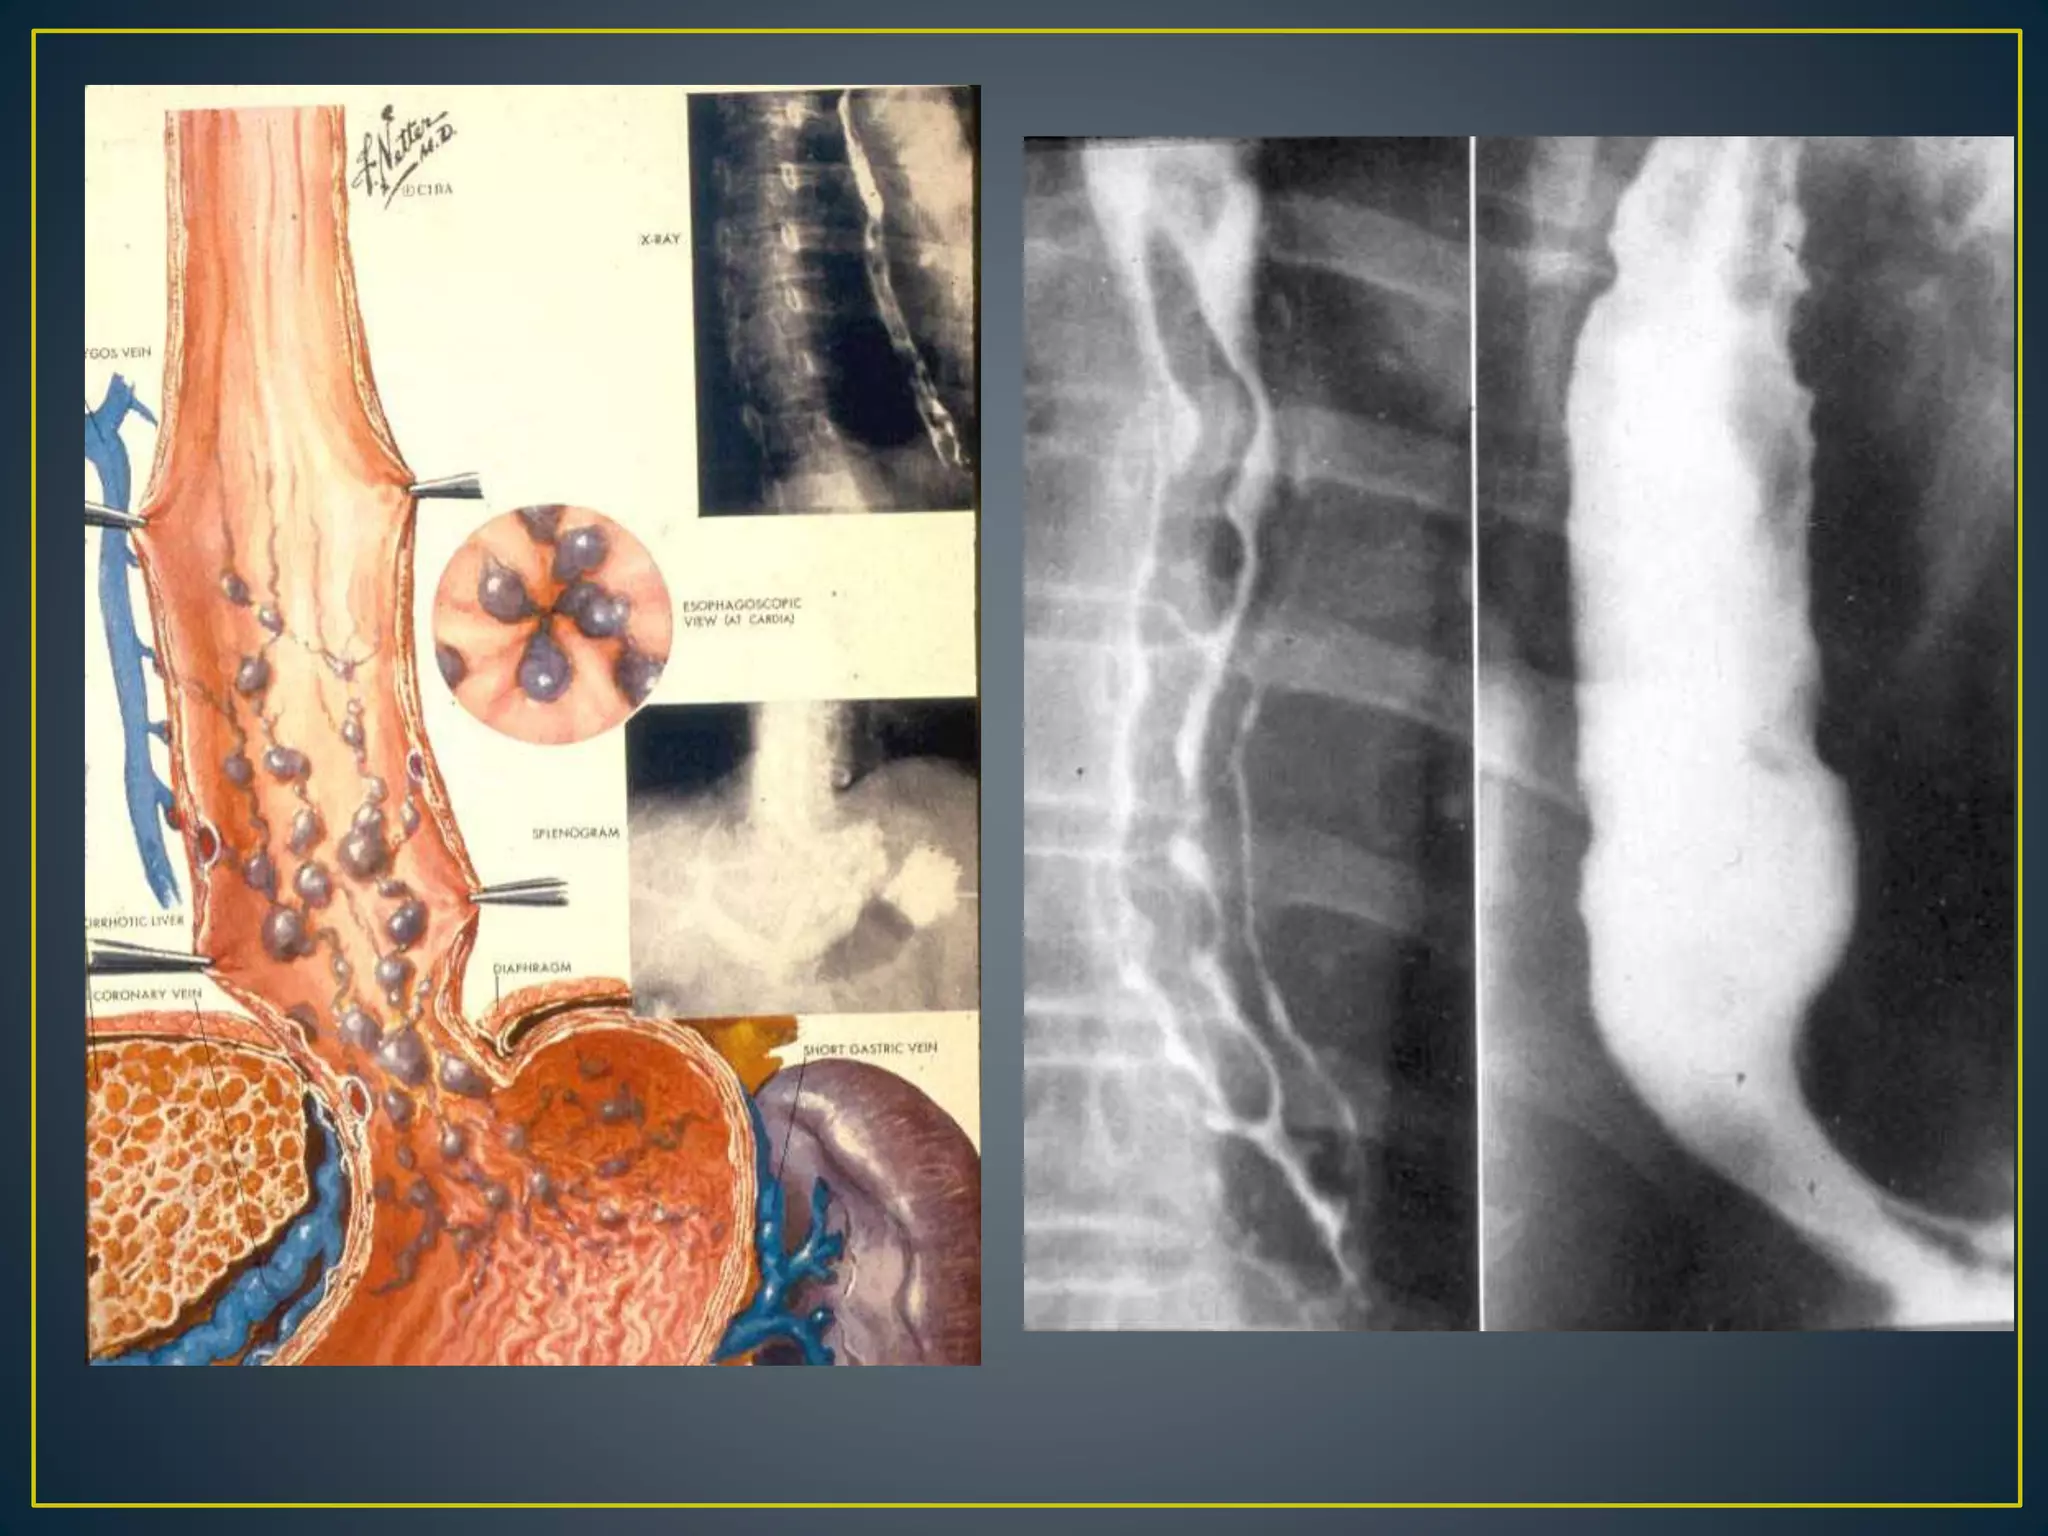

• Variceal bleeding is one of the most alarming life-threatening

• Sixty percent of patients with cirrhosis develop esophageal varices

• Thirty percent of these patients bleed from their varices within 2 years

of their diagnosis

• 50% bleed at some point during their lifetime

• The mortality rate for variceal bleeding is 30-50%, which is much

higher than any other cause of UGIB

1. Serpiginous filling defects which

appear as round or oval filling defects

resembling the beads of a rosary( dilated

venous structures) ( arrowhead).

2. Changes size and appearance with

variations in intrathoracic pressure and

collapse with esophageal peristalsis and

distension.

3. Varices related to portal

hypertension are most commonly

demonstrated in the lower third of the

esophagus.

4. In portal hypertension ; common

accompanying gastric varices(arrow).